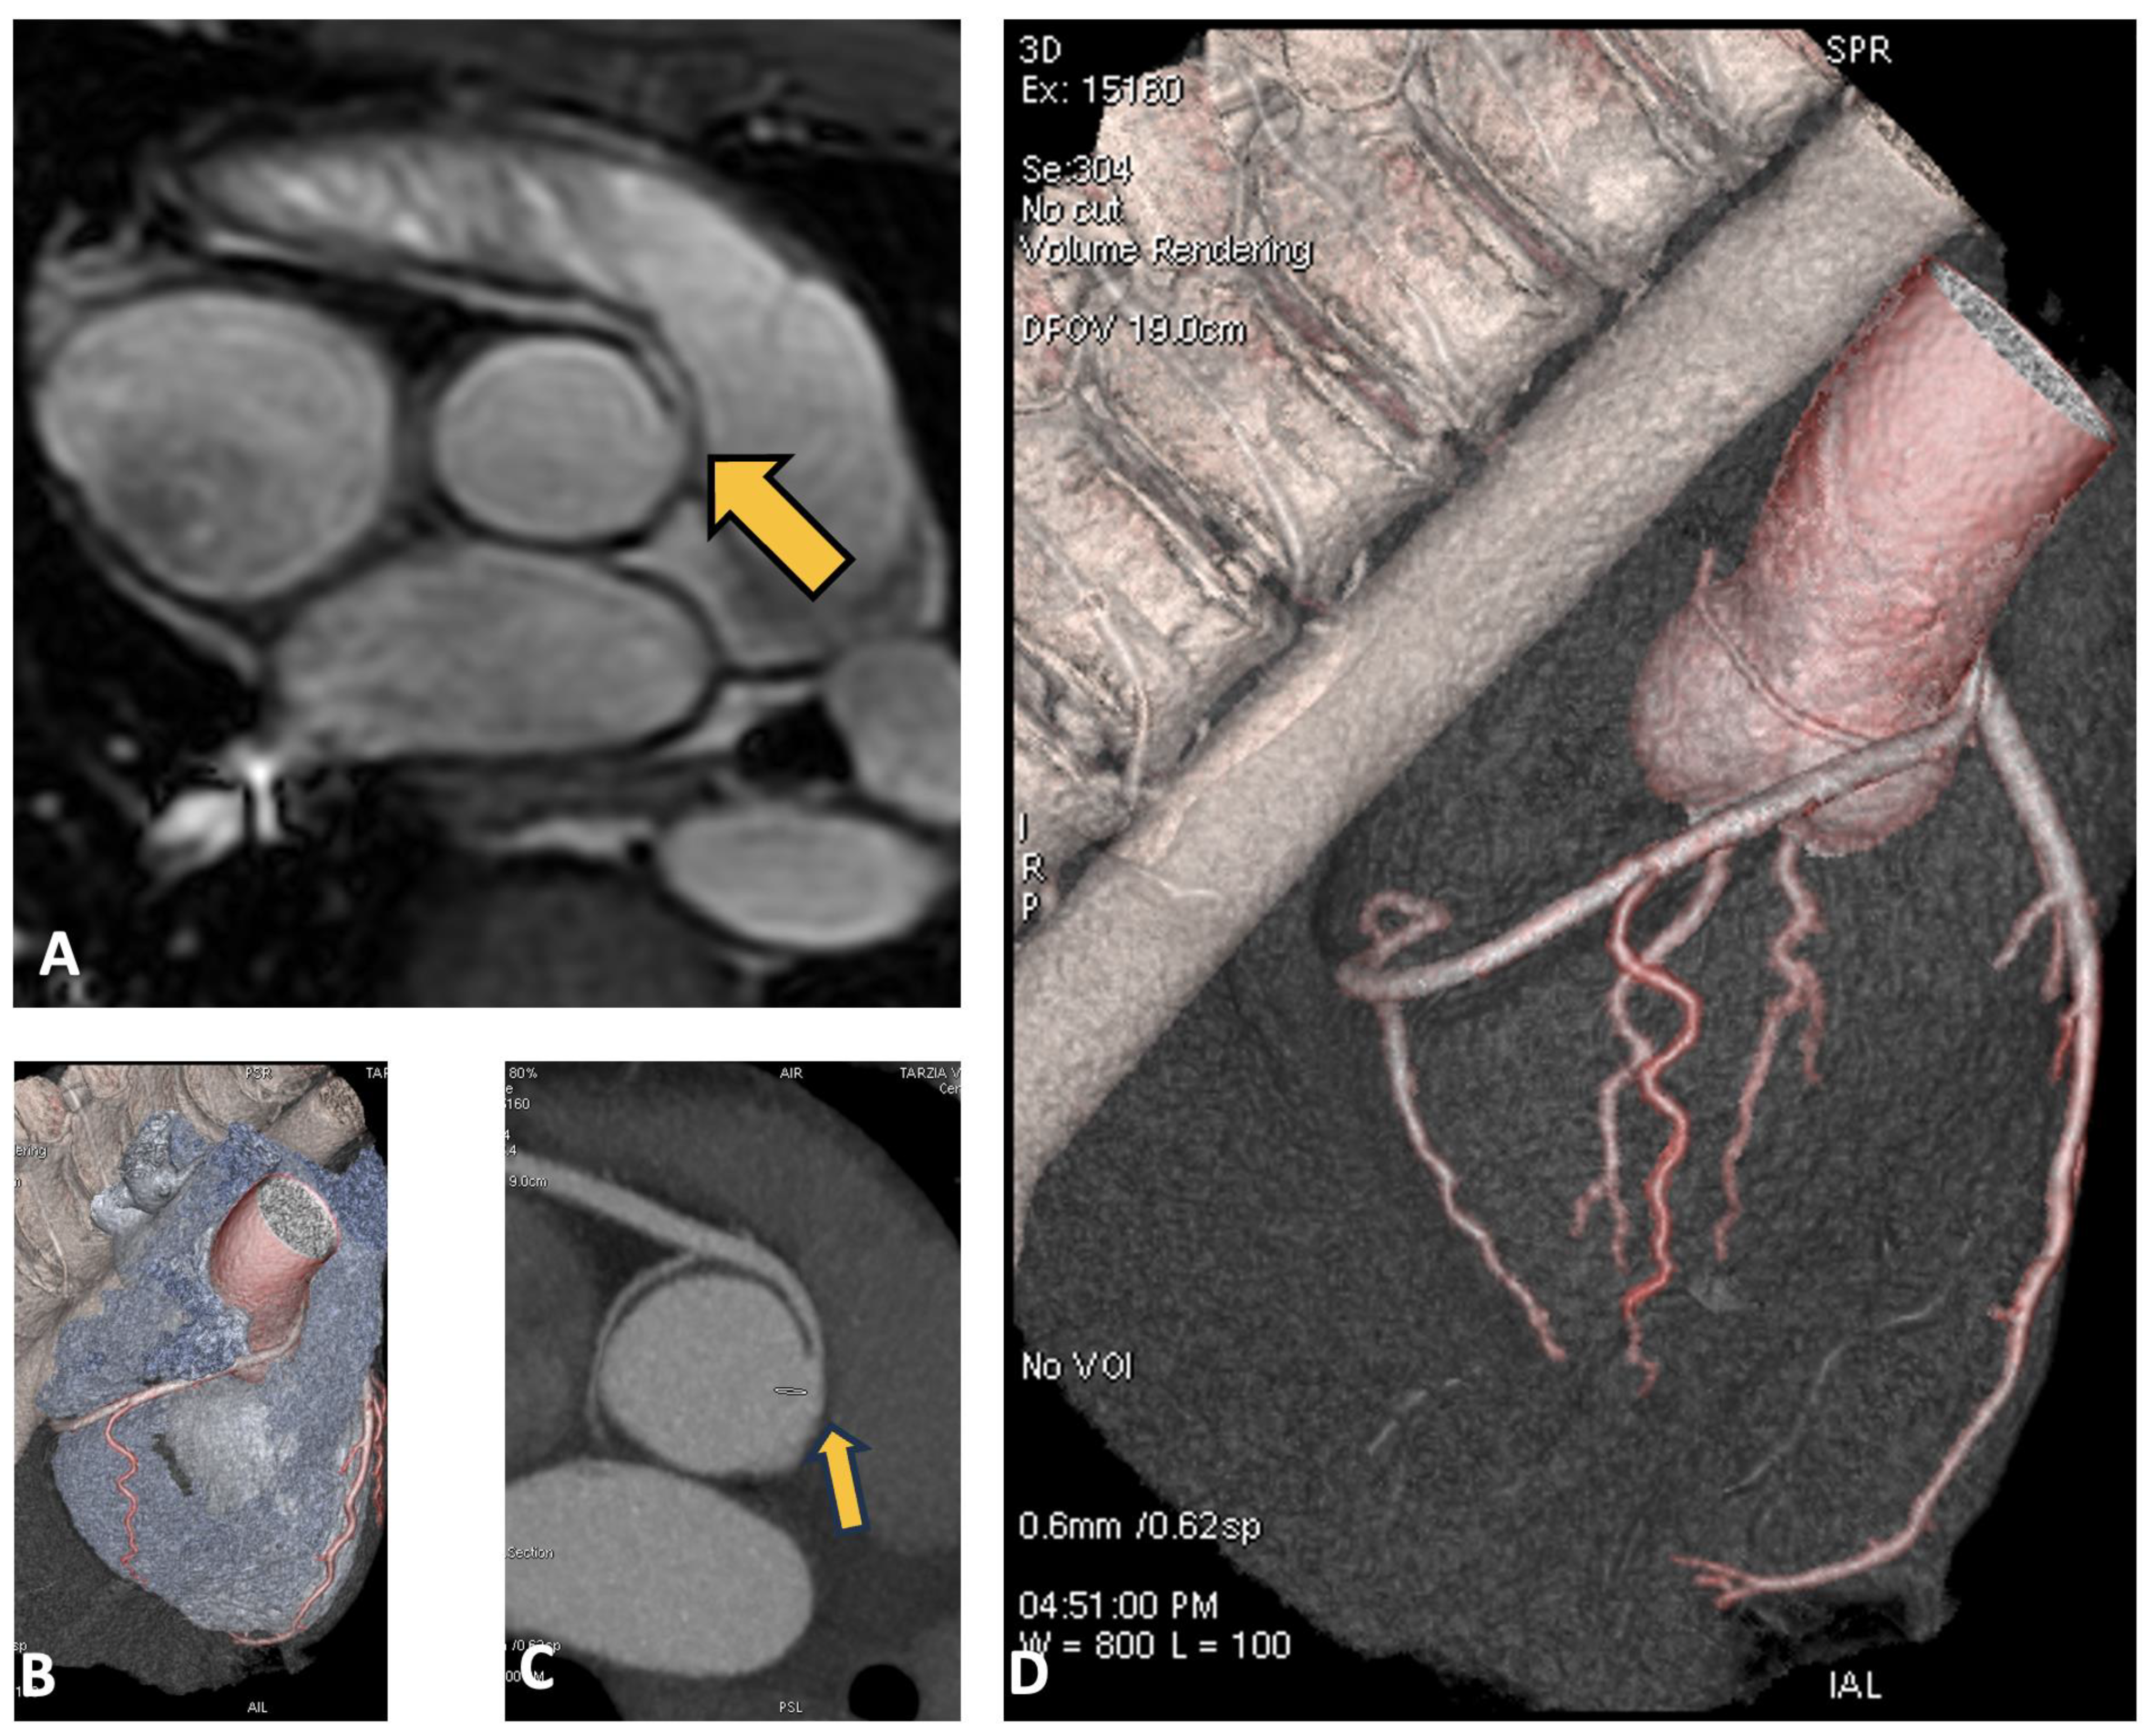

3.4. Case 4: Coronary Fistula

4.3. Coronary Artery Fistula